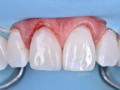

Bezpośrednia licówka kompozytowa w odcinku przednim wykonana…

Michał Jaczewski